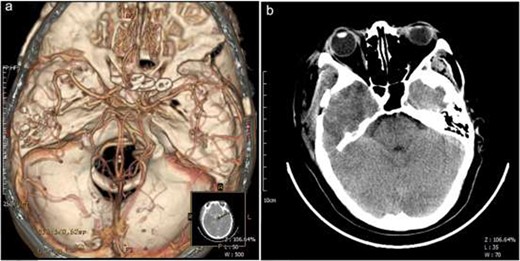

Preoperative imaging examinations, general physical condition and family history of the patient were considered when deciding to perform one-stage operation by coronal incision using a right frontotemporal craniotomy. First, the right zygomatic arch was removed and a bone flap was formed. After hanging the dura, it was cut open to detect lesions, and the tumor was excised along the edge of the lesion. Subsequently, the lesion was repeatedly cauterized at the base of the dura mater using noncondensable bipolar electrocoagulation tweezers. Furthermore, the lateral fissure was separated to expose the internal carotid artery. The aneurysm in the ophthalmic segment of the right internal carotid artery was blocked by the clinoid process, which was removed to expose the proximal and distal ends of the aneurysm. The aneurysm was clipped using an aneurysm clip. The frontal lobe from the right side was raised, the optic chiasm was separated, the left internal carotid artery was exposed, the ophthalmic segment left internal carotid artery aneurysm was detected and the aneurysm was clipped using a combination of two cross-vessel clips (Fig. 2a–f). Figure 3a and b shows a representation of the postoperative pathological diagnosis of the fiber type meningioma (WHO I Level). A postoperative CTA showed complete occlusion of the ophthalmic segment aneurysm of the bilateral internal carotid artery and a CT scan revealed postoperative changes in the right temporal bone, swelling of adjacent scalp soft tissues, and slight gas accumulation (Fig. 4a and b). The patient recovered well from the procedure and was discharged from the hospital.

Postoperative imaging. Postsurgical CTA revealed that bilateral ophthalmic segment internal carotid artery aneurysms were completely obliterated (a); Postsurgical CT showed postoperative changes in the right temporal bone, swelling of adjacent scalp soft tissues, and slight gas accumulation (b). A, anterior; P, posterior; L, left; R, right.